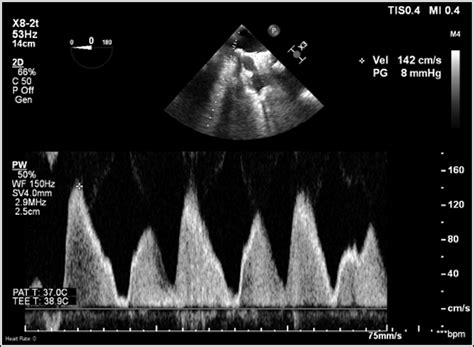

Echocardiogram Uses sound waves to create images of the heart and pulmonary veins, assessing blood flow and detecting any narrowing.

These diagnostic tests help healthcare providers determine the presence and severity of Pulmonary Vein Stenosis, guiding the development of an appropriate treatment plan.